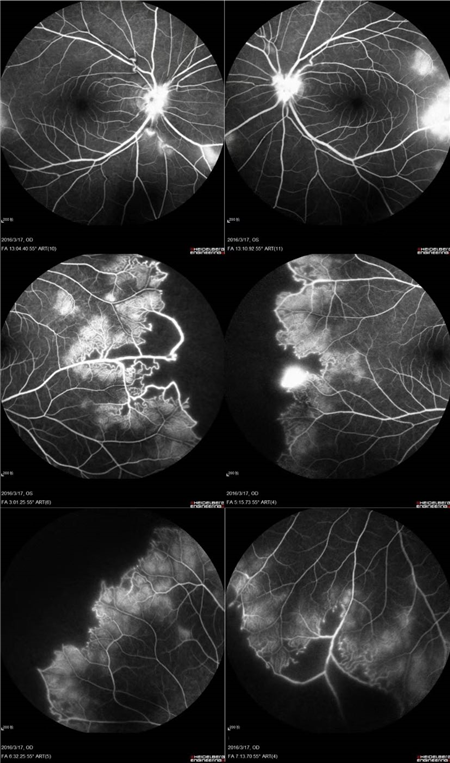

经过详细的眼底检查后,患者被诊断为IRVAN综合征引起的右眼黄斑裂孔,张风院长带领医生团队为患者施局右眼玻璃体切除+剥膜+眼内光凝+气液交换手术,经过半个月的恢复,患者右眼术后视力由术前0.3-达到0.6-的状态,且裂孔呈逐渐闭合状态。

视盘附近的动脉和动脉分叉处出现瘤样动脉扩张,视盘充血,边界不清,引起视盘周围视网膜内硬性渗出;视盘周可有少量放射状出血。

静脉不规则扩张和血管鞘膜,周边部小血管广泛闭塞,交界处毛细血管扩张和异常吻合。

严重者可发生从周边到黄斑的血管闭塞和缺血、玻血、新生血管性青光眼,最终视神经萎缩。

长期追踪发现动脉瘤是一种血管炎性的游走性改变,炎症消失时,血管壁强度恢复,瘤体减小,甚至恢复正常。